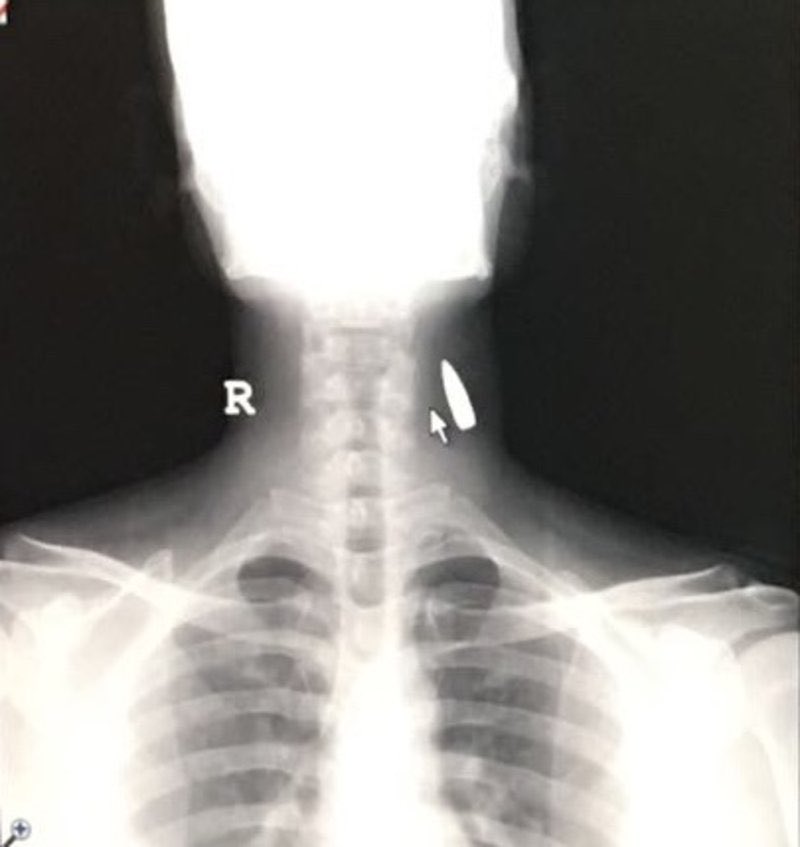

اكيد رصاصة مجهولة وبعدها الآف الرصاصات ما دام أسلحة الموت مفلوتة في أيادي المراهقين والحمقاء من الشعب مسؤولية وزارة الداخلية حظر الأسلحة وسحبها ومنع إقتناءهاpic.twitter.com/CHjwYu99ID

الرصاصه راسها فوق معناتها السلاح كان قريب وموجه مباشر للشخص المجهوله تنزل نزول

السؤال كيف دخلت الرصاصه من تحت لفوق؟ الرصاصه تكون ساقطه...